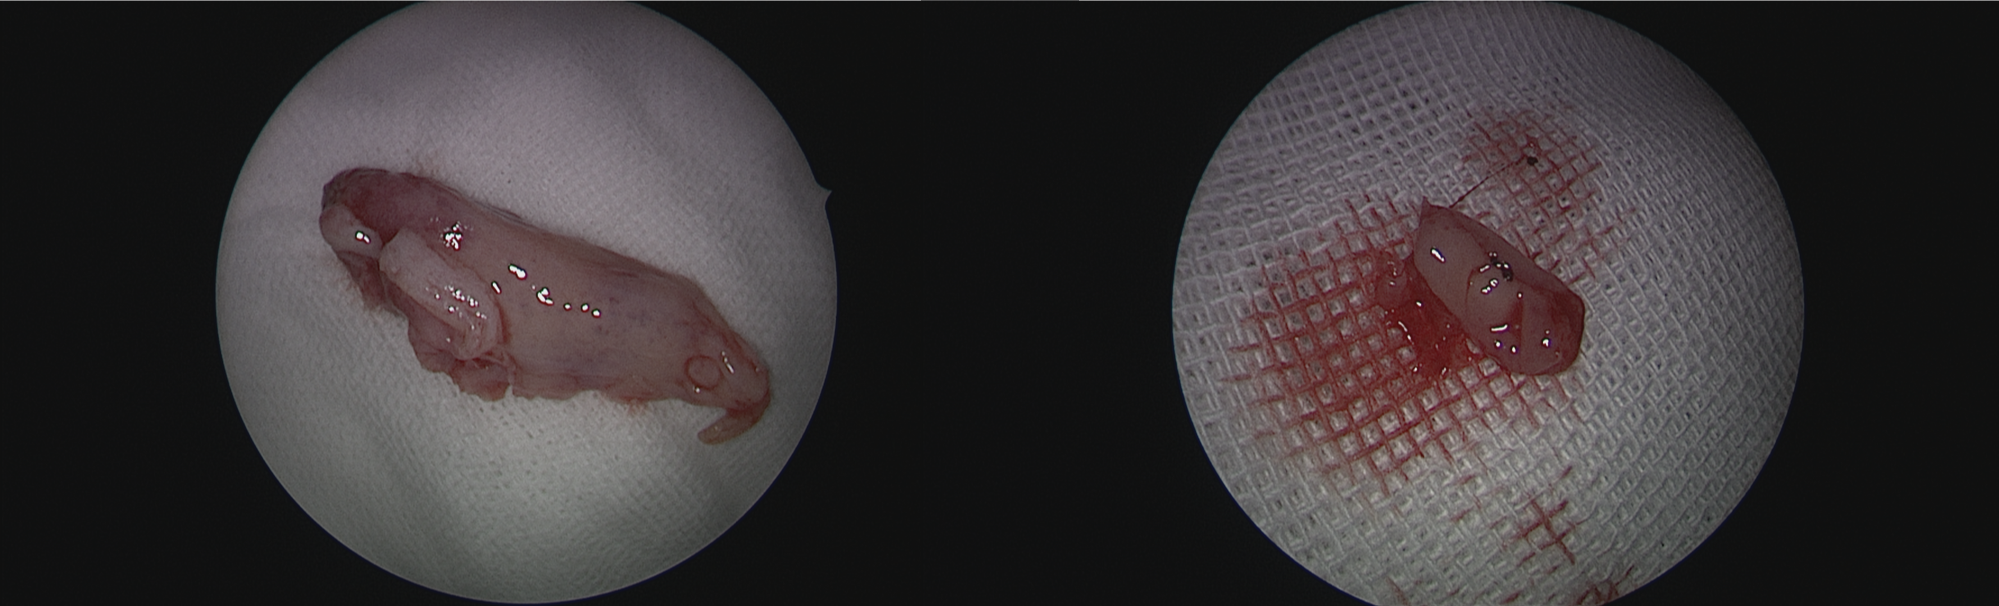

图3.诊断:左侧PPF肿瘤(术后病理:神经鞘瘤)

图4.术中切除的中鼻甲(左)与钩突